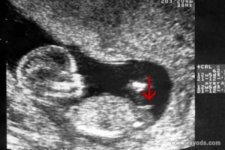

(女孩的nt图片)

首先看nt图中胎儿整个身体的幅度,如果身子是弯着的,说明怀的是男孩,反之如果身子是平行的,则怀女孩,据说很多人都是根据这一点对比男女的不同的。

再者就看胎儿脊柱线和尾椎骨,按照男孩女孩发育的不同,男孩的脊柱线会大于30度甚至更多,身体明显有弯曲的弧度,而女孩的脊柱线一般都是小于30度的,看起来就是平缓的睡在妈妈肚子里。就对于这一点,老人们也有一个说法与之类似,那就是“儿靠女睡”,其意思就是儿子靠着妈妈,女儿则睡在妈妈肚子里。

最后就看胎儿的尾椎骨这里了,据说胎儿尾椎骨上翘的话则说明怀的是男孩,反之如果尾椎骨和身体保持平行的话则生女孩。尾椎骨是男女特征最大的区别点,因为这个地方是要发育生殖器的,尤其是男孩尾椎骨会上翘,这是在给生殖器发育留下空间,因此才会有这个姿势。